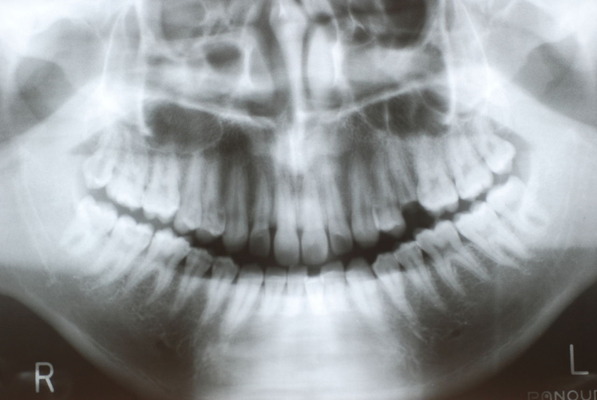

ある方の例です。親不知が痛くなってきました。一見問題ないようです。でも歯周病を常に治療している優れた歯科医師ならば、乾燥させてみた歯茎の色の変化で殆ど歯周病罹患部を指摘できるそうです。

検査をすれば恐ろしいほどの状態だといえるのです。10年後は虫歯と歯周病で残っている歯は何本なのか心配になってきました。

初診から数週間後大分よくなったとはいえまだまだ簡単な検査でも血だらけなのですね。